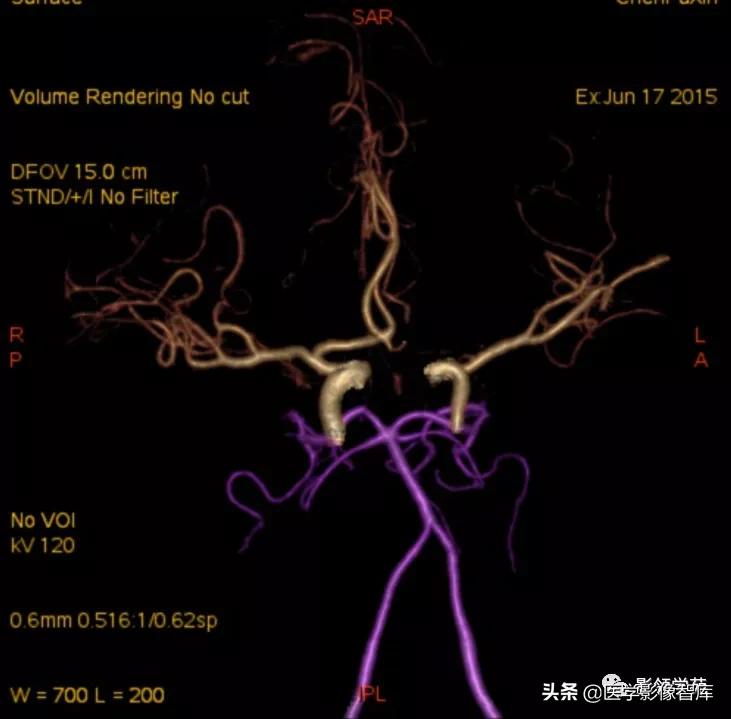

- DSA-金标准、最可靠,但有创,且不能显示完全血栓化的动脉瘤,而CT、MRI则可显示。(CTA、MRA可诊断,尤其是MSCTA具有较高的敏感性和特异性。)

女 58岁,头晕、呕吐,桥脑右前方见一类圆形

高低混合(有血栓)T1及T2信号影,边界清楚、锐利。

明显不均匀强化(瘤内有血栓)。与基底动脉分界不清

头颅CTA:基底动脉起始部血管局部瘤样突起(宽基底),无占位效应。

女 72岁,发现糖尿病3年余

鞍上区见一团块状稍高密度影,边界尚清,密度均匀。

鞍上右上方见一类椭圆形流空影。

病灶明显强化(瘤内血栓未强化),边界清楚,与右侧颈内动脉海绵段分界不清。垂体大小、形态未见异常。